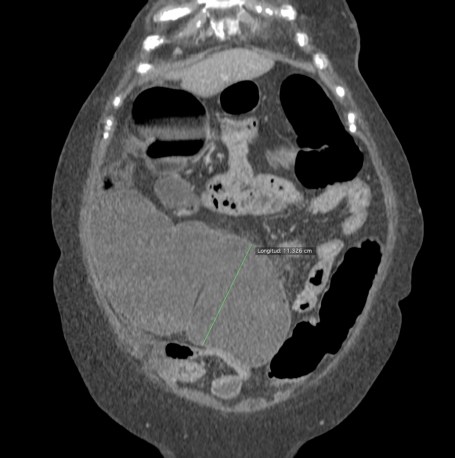

Se realiza placa de abdomen y TC en vacío y fase portal.

El cuadro oclusivo está producido por una litiasis biliar que ha pasado de la vesícula al intestino a través de una fístula con el duodeno y que llegó hasta el recto por una insuficiencia de la válvula ileocecal. Así, se produjo una dilatación generalizada de asas, principalmente de las del intestino grueso, que finalmente derivó en isquemia intestinal.